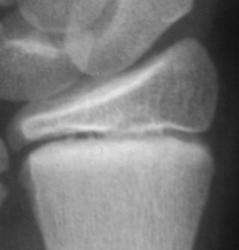

Травма. Пациент направлен хирургом в рентгеновский кабинет для рентгенологического исследования лучезапястного сустава.

Вот она - натуральная  "зеленая ветка"!!!

показательный снимок этого перелома